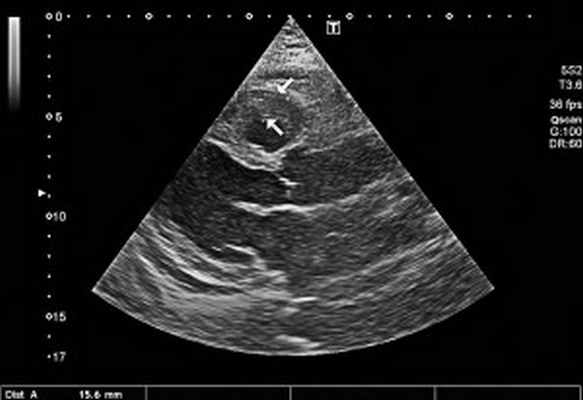

- Ультразвуковые исследования.ЭхоКГ выявляет утолщение в области верхушки сердца, которое ассоциируется с фиброзным процессом или тромботическими отложениями. Исследование подтверждает утолщение и деформацию хорд, створок клапанов (главным образом, трикуспидального и митрального). Ультразвуковая допплерография сердца определяет нарушение гемодинамики в камерах органов – вентрикулоатриальную регургитацию крови.

При рентгенологическом обследовании органов грудной клетки обнаруживают кардиомегалию и признаки венозного застоя в легких. Изменения ЭКГ не специфичны. Частые находки – нарушения ритма сердца, особенно фибрилляция предсердий (ФП). В диагностике заболевания основную роль играет эхокардиография (ЭхоКГ), позволяющая обнаружить локальное (реже – диффузное) утолщение верхушки одного или обоих желудочков с вовлечением в патологический процесс хорд, умеренную митральную или трикуспидальную регургитацию, пристеночные, особенно верхушечный, крупные тромбы. Показательным является «рестриктивный тип» ремоделирования сердца и внутрисердечной гемодинамики – очевидное преобладание объема предсердий над объемами желудочков. Систолическая функция, как правило, сохранена, но диагностируется диастолическая дисфункция – рестриктивный тип трансмитрального/транстрикуспидального кровотока. Наиболее информативными методами исследования на сегодняшний день являются магнитно-резонансная томография (МРТ) и мультиспектральная компьютерная томография с контрастированием 14. В литературе описан случай динамического наблюдения за развитием эндокардита Леффлера с серией одновременно производимой позитронно-эмиссионной томографии и контрастированной МРТ с выделением стадий: бессимптомной, острой некротической, симптомной тромботической и фибротической [13]. Выполнение эндомиокардиальной биопсии миокарда правого (ПЖ) или левого (ЛЖ) желудочка позволяет подтвердить или опровергнуть диагноз эндокардита Леффлера.

Рис. 2. Неравномерное значительное утолщение стенок ПЖ (парастернальный доступ, позиция по длинной оси)